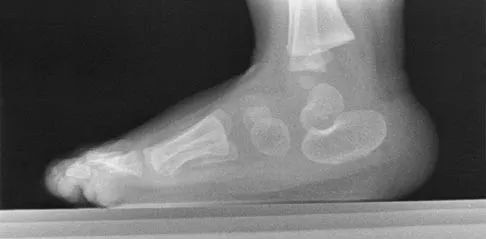

An obese 62-year-old man reports a 10-year history of progressive flatfoot deformity and a 3-month history of a painful callus along the plantar medial midfoot that has not improved with custom shoe wear, pedorthics, and callus care. There is no hindfoot motion, but functional ankle motion remains. He does not have diabetes mellitus. Radiographs are shown in Figures 27a and 27b. What is the best surgical option at this point?

Explanation

The deformity is long-standing, the hindfoot is immobile, and the radiographs reveal severe degenerative arthritis involving the entire hindfoot, severe deformity, and talonavicular dislocation. The "exostosis" responsible for the callus is the talar head; resection would severely destabilize the foot. Degenerative arthritis and fixed deformity preclude lateral column lengthening, medial slide calcaneal osteotomy, and talonavicular arthrodesis. Triple arthrodesis is the only viable option. Johnson JE, Yu JR: Arthrodesis techniques in the management of Stage II and III acquired adult flatfoot deformity. Instr Course Lect 2006;55:531-542.